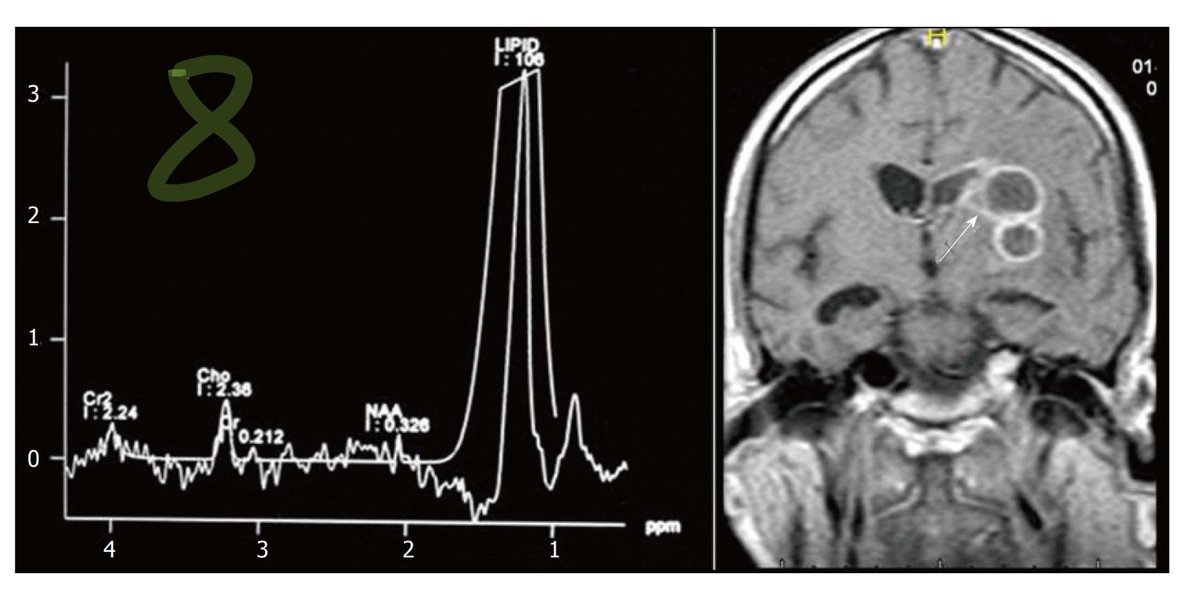

Differentiating of ring enhancing etiologies:

DWI of bacterial & tubercular show central restriction, whereas fungal shows wall & projections restriction, though not core

MR spectroscopy of bacterial shows amino acids peaks, tubercular lipids peaks, whereas fungal multiple peaks ImageImage

8:Toxoplasmosis, Gd enhancement, no DWI restriction, decreased perfusion, MRS lipid peaks.